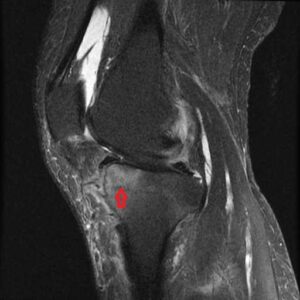

膝関節MRIでみられる骨髄浮腫 (bone marrow edema:BME)は、痛みの強さを表します。

MRI BME Lat